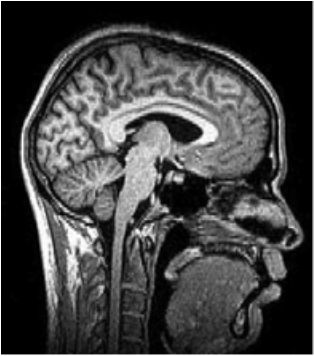

1. The image represents what type of slice?

A. Sagittal

B. Horizontal

C. Coronal

D. Axial

2. All of the following structures can be seen in the figure EXCEPT

A. Cerebellum

B. Corpus callosum

C. Lateral ventricles

D. Cerebral cortex

3. The figure illustrates which imaging model?

A. CT

B. PET

C. Magnetoencephalography (MEG)

D. MRI